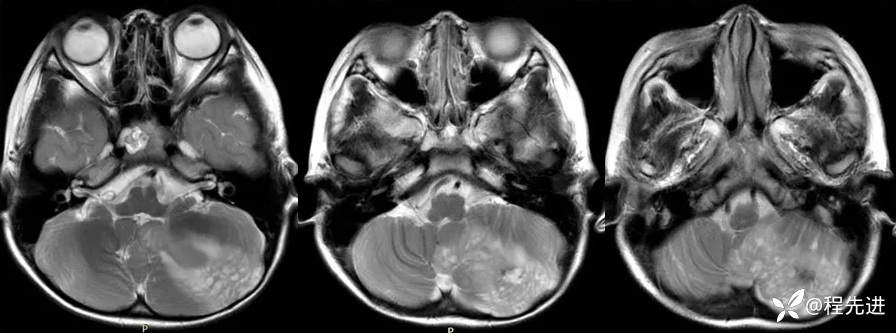

【患者信息】:男,6岁

【主诉】:查体发现左侧小脑半球占位3个月

【现病史及既往史】:患者3个月前因鼻塞至外院就诊,行头颅CT检查偶然发现颅内占位

【检查】